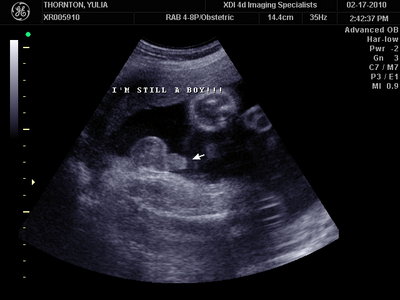

А это в 30 недель

| Вложения: |

MY BABY SONO!_20.JPG [ 94.63 КБ | Просмотров: 1046 ]

Sweetheart75 писал(а): Ну ладно, тогда и я нашего писюна покажу  Надеюсь, Джеффри на меня не обидится Вот это в 23 недели: (там оборудование переключалось из режима 3Д в обычный 2Д) Oоо, такое достоинство невозможно не заметить  А в 30 недель так вообще!